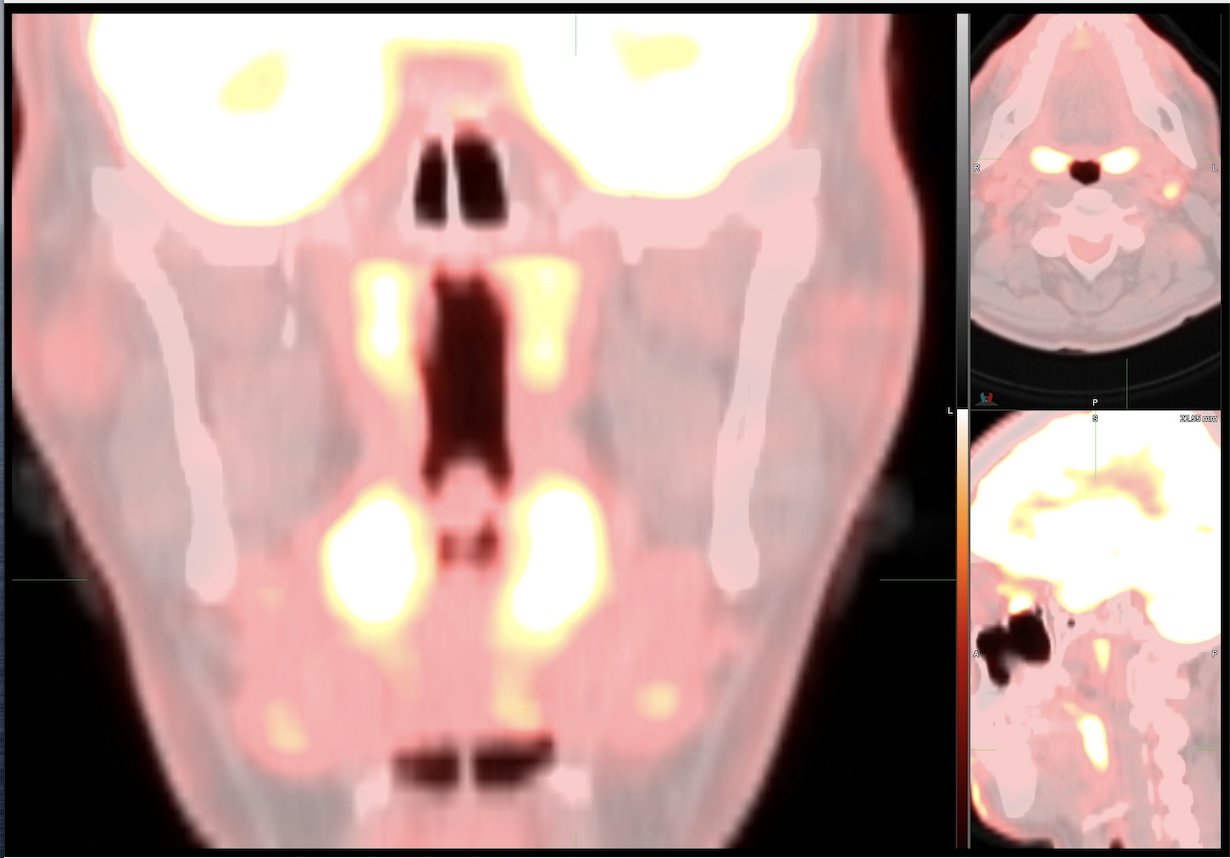

This photo gallery shows the variety of radiological presentations of COVID-19 (SARS-CoV-2) in medical imaging, including computed tomography (CT), radiograph X-rays, ultrasound, echocardiograms and magnetic resonance imaging (MRI). The radiology images show examples of typical COVID pneumonia in the lungs and the numerous complications the virus causes in the body in multiple organs, including the brain, kidneys, heart, abdomen and vascular system.